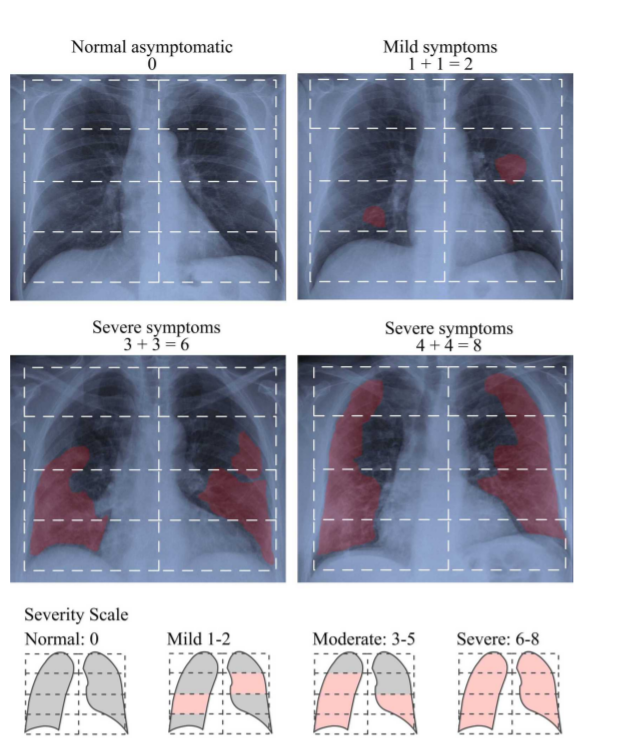

폐 부종을 평가하는 스코어(RALE)를 접목시킴으로써 쉽게 severity를 측정하고자 했다.

RALE score 는 consolidation, ground glass opacities 를 기준으로 각 폐에 0-4 사이의 점수를 준다.

아래 사진에서 볼 수 있듯이 흉부 사진을 8개의 구역으로 나누고, 한 구역에 위에서 언급했던 특징(consolidation, ground glass opacities)가 나타나면1점씩 주는 방식이다.

Figure 1

Normal      0

Mild         1-2

Moderate  3-5

Severe      6-8